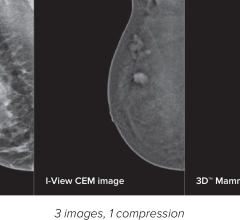

Three-D mammography is also commonly called digital breast tomosynthesis, or DBT. The technology combines low-dose X-rays with software that creates a 3-D image of the breast. Compared to 2-D mammography, DBT may make it easier for radiologists to detect an abnormality. Yet DBT has not been widely endorsed for routine breast cancer screening. Organizations like the U.S. Preventive Services Task Force and the American Cancer Society, which provide guidance to clinicians about cancer screening, have not made recommendations for or against the routine use of DBT.